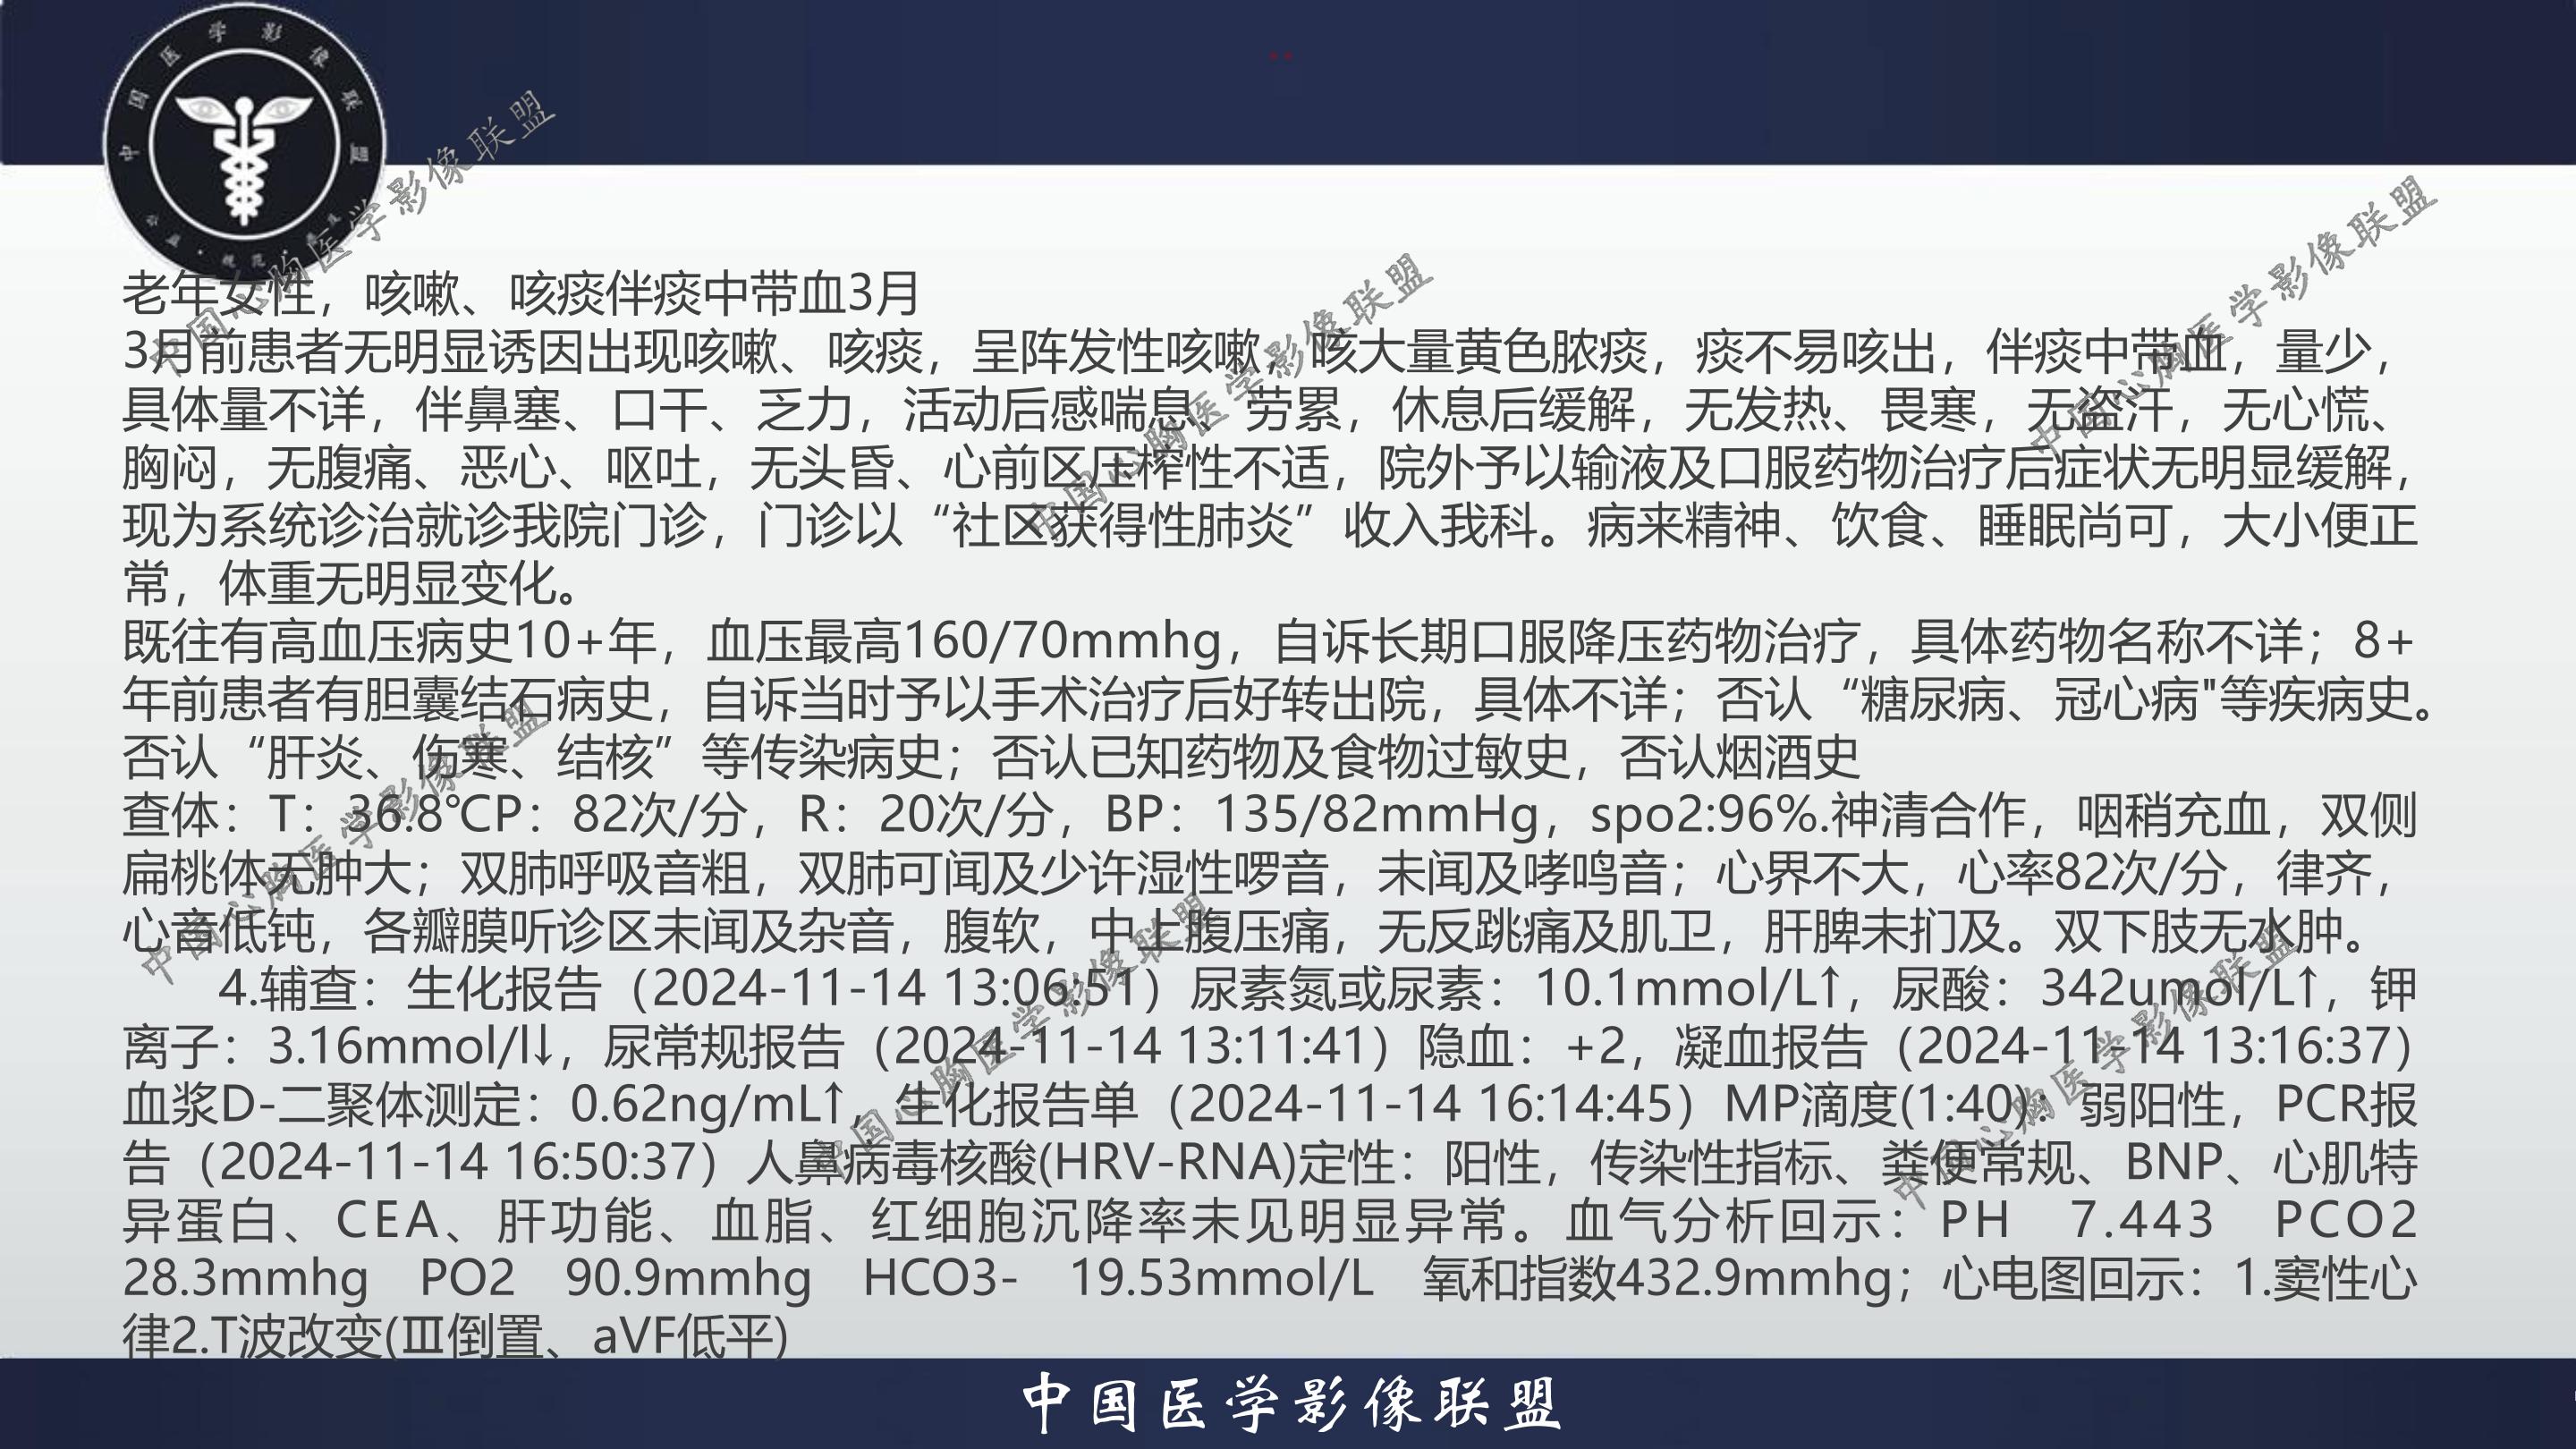

老年女性,咳嗽、咳痰伴痰中带血3月

3月前患者无明显诱因出现咳嗽、咳痰,呈阵发性咳嗽,咳大量黄色脓痰,痰不易咳出,伴痰中带血,量少,具体量不详,伴鼻塞、口干、乏力,活动后感喘息、劳累,休息后缓解,无发热、畏寒,无盗汗,无心慌、胸闷,无腹痛、恶心、呕吐,无头昏、心前区压榨性不适,院外予以输液及口服药物治疗后症状无明显缓解,现为系统诊治就诊我院门诊,门诊以“社区获得性肺炎”收入我科。病来精神、饮食、睡眠尚可,大小便正常,体重无明显变化。

既往有高血压病史10+年,血压最高160/70mmhg,自诉长期口服降压药物治疗,具体药物名称不详;8+年前患者有胆囊结石病史,自诉当时予以手术治疗后好转出院,具体不详;否认“糖尿病、冠心病"等疾病史。否认“肝炎、伤寒、结核”等传染病史;否认已知药物及食物过敏史,否认烟酒史

查体:T:36.8℃P:82次/分,R:20次/分,BP:135/82mmHg,spo2:96%.神清合作,咽稍充血,双侧扁桃体无肿大;双肺呼吸音粗,双肺可闻及少许湿性啰音,未闻及哮鸣音;心界不大,心率82次/分,律齐,心音低钝,各瓣膜听诊区未闻及杂音,腹软,中上腹压痛,无反跳痛及肌卫,肝脾未扪及。双下肢无水肿。

4.辅查:生化报告(2024-11-14 13:06:51)尿素氮或尿素:10.1mmol/L↑,尿酸:342umol/L↑,钾离子:3.16mmol/l↓,尿常规报告(2024-11-14 13:11:41)隐血:+2,凝血报告(2024-11-14 13:16:37)血浆D-二聚体测定:0.62ng/mL↑,生化报告单(2024-11-14 16:14:45)MP滴度(1:40):弱阳性,PCR报告(2024-11-14 16:50:37)人鼻病毒核酸(HRV-RNA)定性:阳性,传染性指标、粪便常规、BNP、心肌特异蛋白、CEA、肝功能、血脂、红细胞沉降率未见明显异常。血气分析回示:PH 7.443 PCO2 28.3mmhg PO2 90.9mmhg HCO3- 19.53mmol/L 氧和指数432.9mmhg;心电图回示:1.窦性心律2.T波改变(Ⅲ倒置、aVF低平)